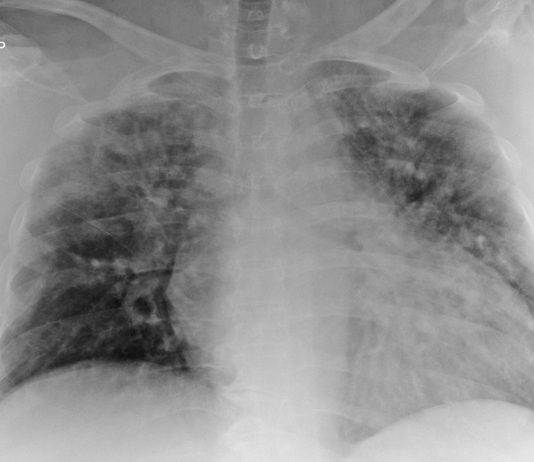

R. Bonacini, G. Besutti, P. PattaciniRadiologia IRCCS Reggio Emilia; Direttore Pierpaolo Pattacini

64-year-old male

with dyspnea, cough and fever for 3 days. Blood test: C-PR 13.44 mg/dl, procalcitonin and CBC

unremarkable. Medical history: DM, HTA.

Chest radiography: